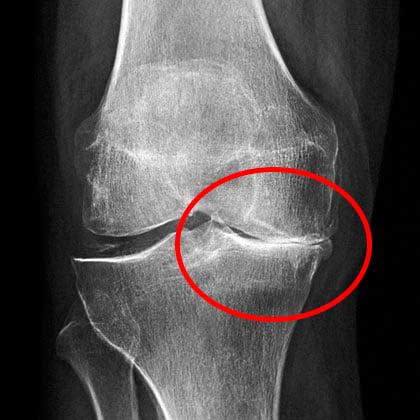

The condition of my knee at that time. Severe pain.

At the appointment, the doctor looked at the pictures for a long time and said that I should no longer do physical labor. And he forbade me to lift anything heavier than 2 kg.

X-rays showed serious problems with my knee.

And this is what my healthy knee looks like now.